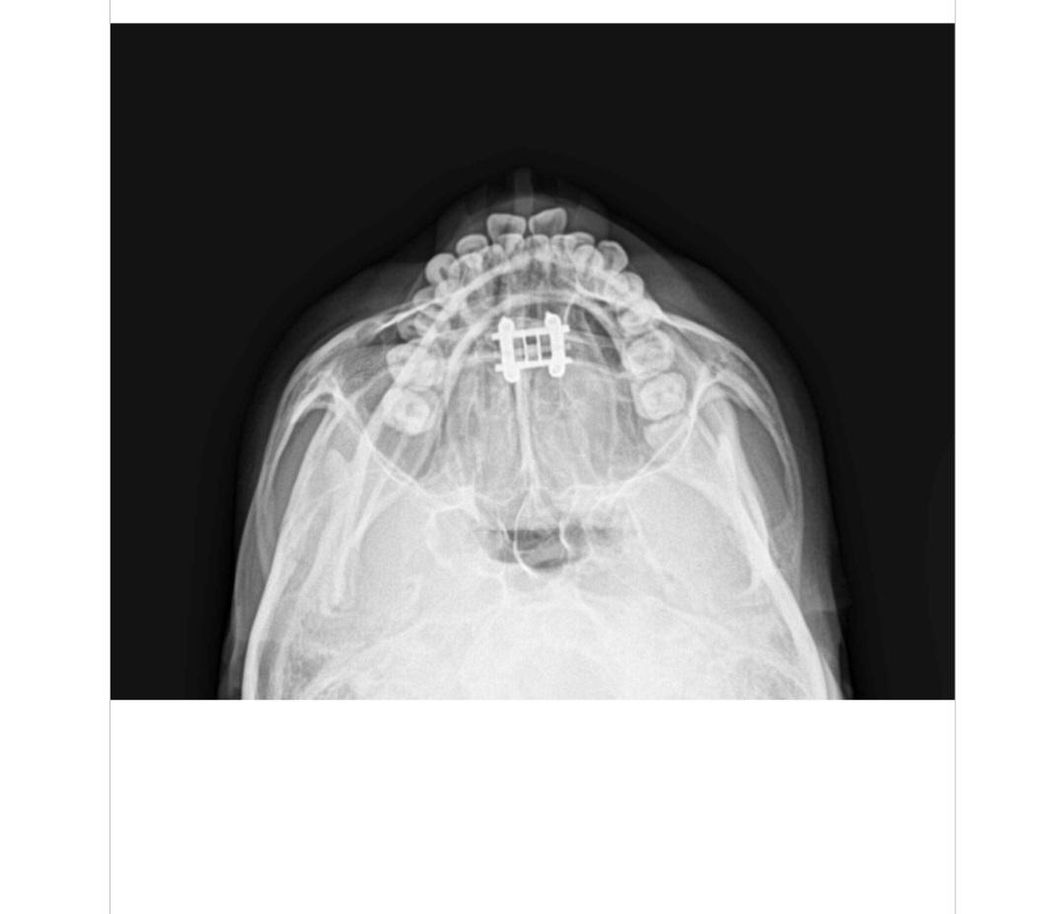

얼굴뼈가 커지는병 도와주세요 엑스레이사진

7월달에 제가 성형외과에서 잰 옆광대수치가 12.6cm였습니다 어제 정형외과병원에서 동일한자세로 턱들고 찍은수치가15.8cm로 4개월만에 옆광대거리가 성인21살인데도 3.2cm이상이 자랐는데 어떻해야할지모르겠습니다작년과 올해5월에 말단비대증피검사를 한번해서 정상이나왔습니다첫번째사진이 7월 두번째사진이 어제찍은사진인데 뼈가 많이 넓어졌는데 원인을모르겠어요..marpe악궁확장을 많이돌려서 넓어진걸까요

• 1번 째 사진